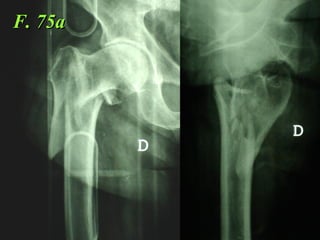

F. 75a